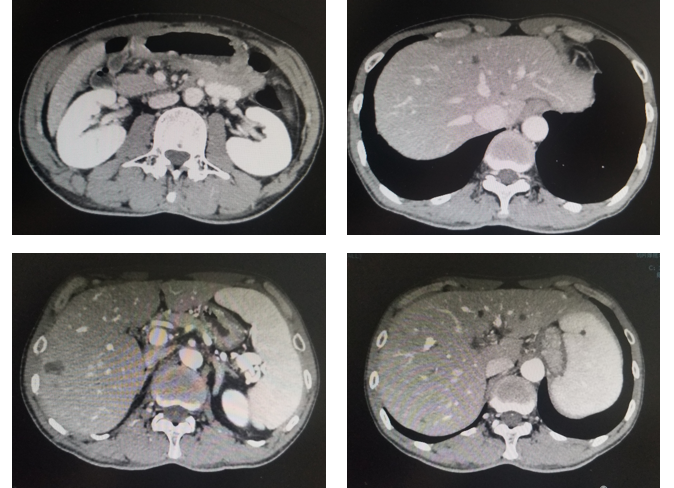

评估:治疗后3月和5月复查腹部CT情况(图2和图3).

图3. 腹部CT平扫+强化(治疗后2月,2020年1月)

影像科:根据患者治疗前、治疗后首次及再次复查CT看,原发病灶胃壁增厚明显减轻,肝转移病灶明显缩小,部分病灶消失,首次CT判效PR,再次复查CT确认PR。提示内科治疗有效。